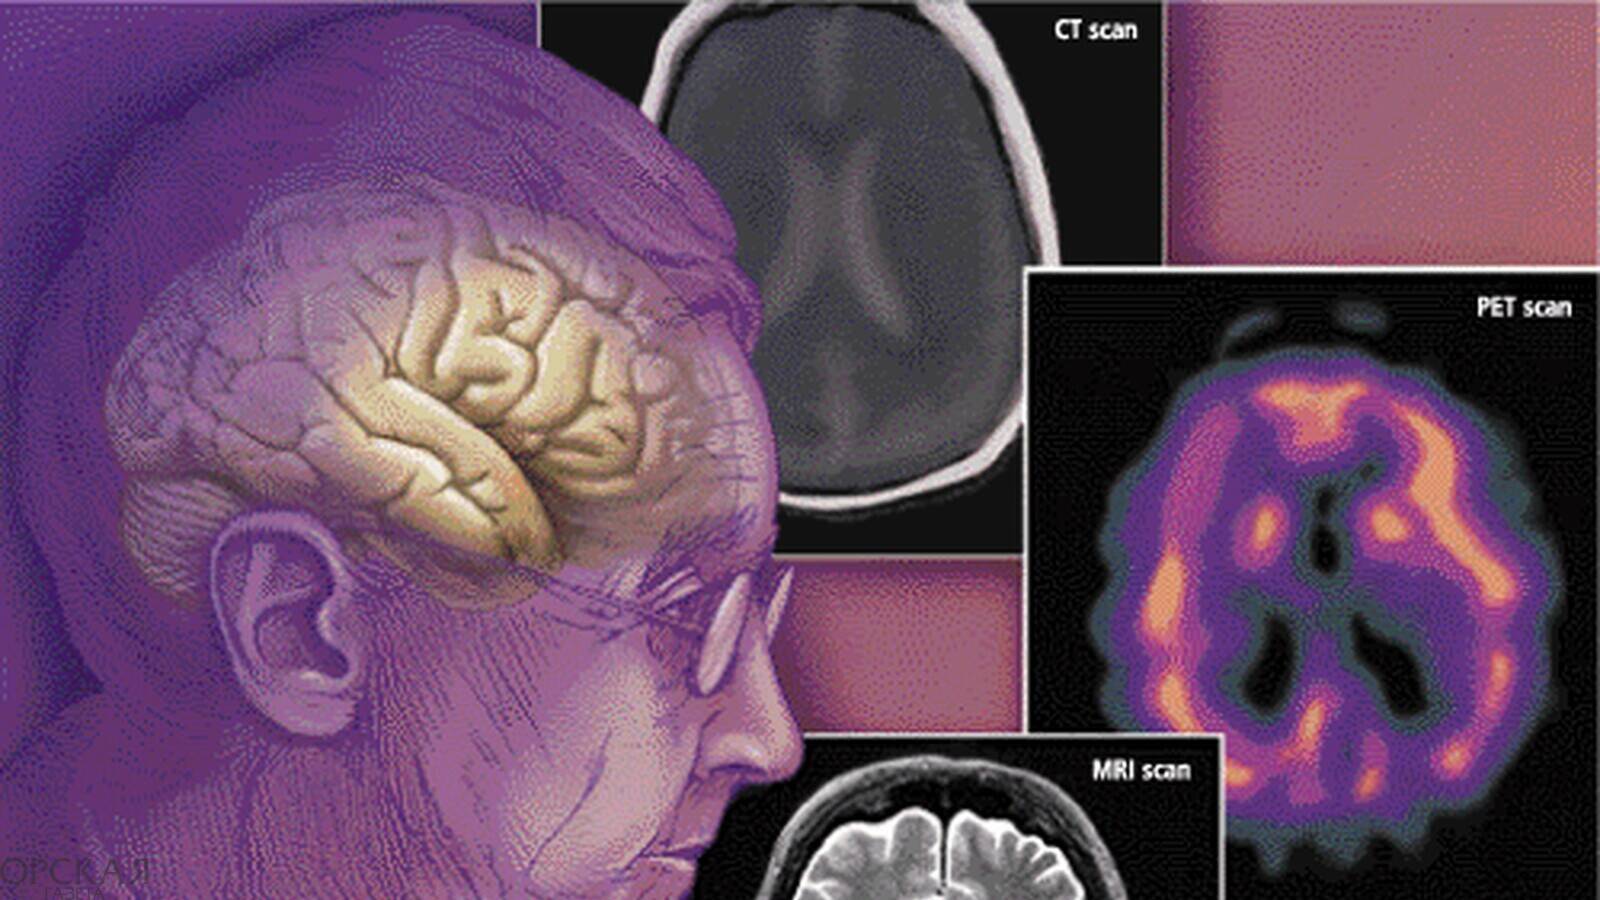

mozg-zdorove-pensioner-starost